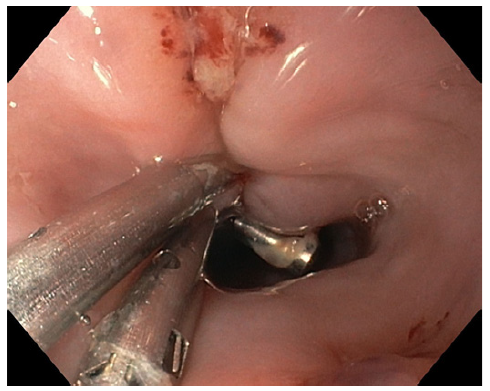

Upper digestive endoscopy was performed, with CO2 insufflation in the operating room in the presence of the general surgery team, under orotracheal intu-bation, and it identified a bone perforation 23 cm from the upper dental arch - the bone was removed with forceps only after unlocking and deflating the endotracheal tube cuff due to space conflict. After extracting the bone, a 15 mm esophageal perforation (shown in Fig. 2) was closed with 4 through-the-scope (TTS) clips (shown in Fig. 3).

In this case, it was necessary to unblock and deflate the orotracheal tube cuff due to space conflict, in order to allow for the bone to be removed. Although the size of this

perforation was >10 mm, and attending to space conflict, closure with TTS clips was tried and successful - clinical judgment is always imperative. This case underscores the efficacy of endoscopic therapy for esophageal perforations and emphasizes the need for multidisciplinary involvement.